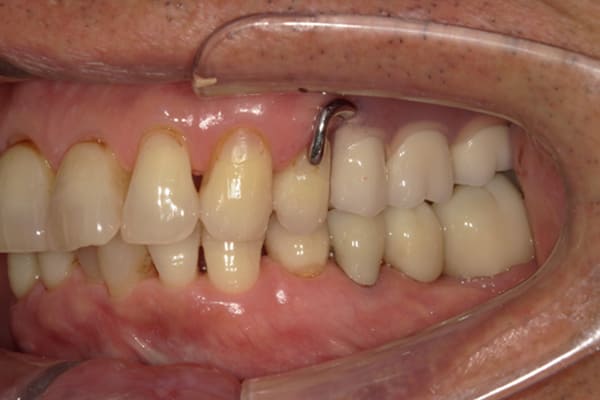

症例レポート[CASE.06]

- 男性(70代)

- 下歯がぐらぐらで抜けそうで痛い、何でも咬めるようにしてほしい

- 治療

- 上顎精密金属床部分入れ歯

- 下顎精密金属床部分入れ歯

- 陶材焼付鋳造冠 4歯

- 磁性アタッチメント 1歯

- 治療期間

-

- 上顎精密金属部分入れ歯:55万円

- 下顎精密金属部分入れ歯:77万円

(治療用義歯含、咬合平面等修正) - 陶材焼付鋳造冠:16.5万円×3歯

(ミリング加工) - 陶材焼付鋳造冠:14.3万円×1歯

(ミリングなし) - 磁性アタッチメント:11万円×1歯

(白金加金)

合計:157.3万円(税込)

奥歯がなくなり放置されていたため、前歯に負担がかかり、歯周病も併発されており歯がぐらぐらでお痛みも伴う状態でした。

可能な限り残せる歯は保存し虫歯治療を行い、どうしても残せないお痛みの歯のみ抜歯を行いました。

陶材焼着付鋳造冠 ミリングラべット加工

残りの歯が少ない場合は、入れ歯が動きやすく、またご自身の歯にも負担がかかるため、残りの歯の被せ物、入れ歯ともに、歯に負担がかかることを最小限にした特殊な加工を行い、歯を長持ちさせる設計としました。

上の入れ歯

下の入れ歯

上の入れ歯は、治療用入れ歯において、前方に違和感を訴えられていたため、違和感のない範囲を治療用入れ歯で決定し、最後の入れ歯に反映することで、上下ともに初めての入れ歯でしたが、違和感を感じることなくご使用になられることが可能になりました。

このように、お一人おひとり、お口の中の感覚は個人差が非常に大きいため、治療用の入れ歯でかみ合わせ、見た目、違和感、お痛みなど、あらゆる項目をチェックし、ご意見をお伺いし、ご相談のうえ最終的な入れ歯の設計を行い作製することで、その方に合った入れ歯が出来上がります。